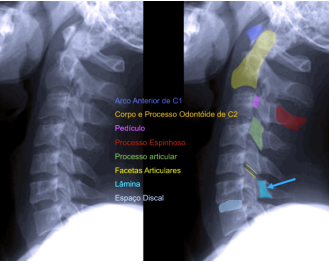

2. Perfil:

Aparecem as vértebras até C7 (coluna cervical)

1. Processo transverso

2. Pedículo

3. Processo articular superior

4. Pars interarticularis

5. Lâmina

6. Processo articular inferior

7. Processo espinhoso

8. Espaço discal